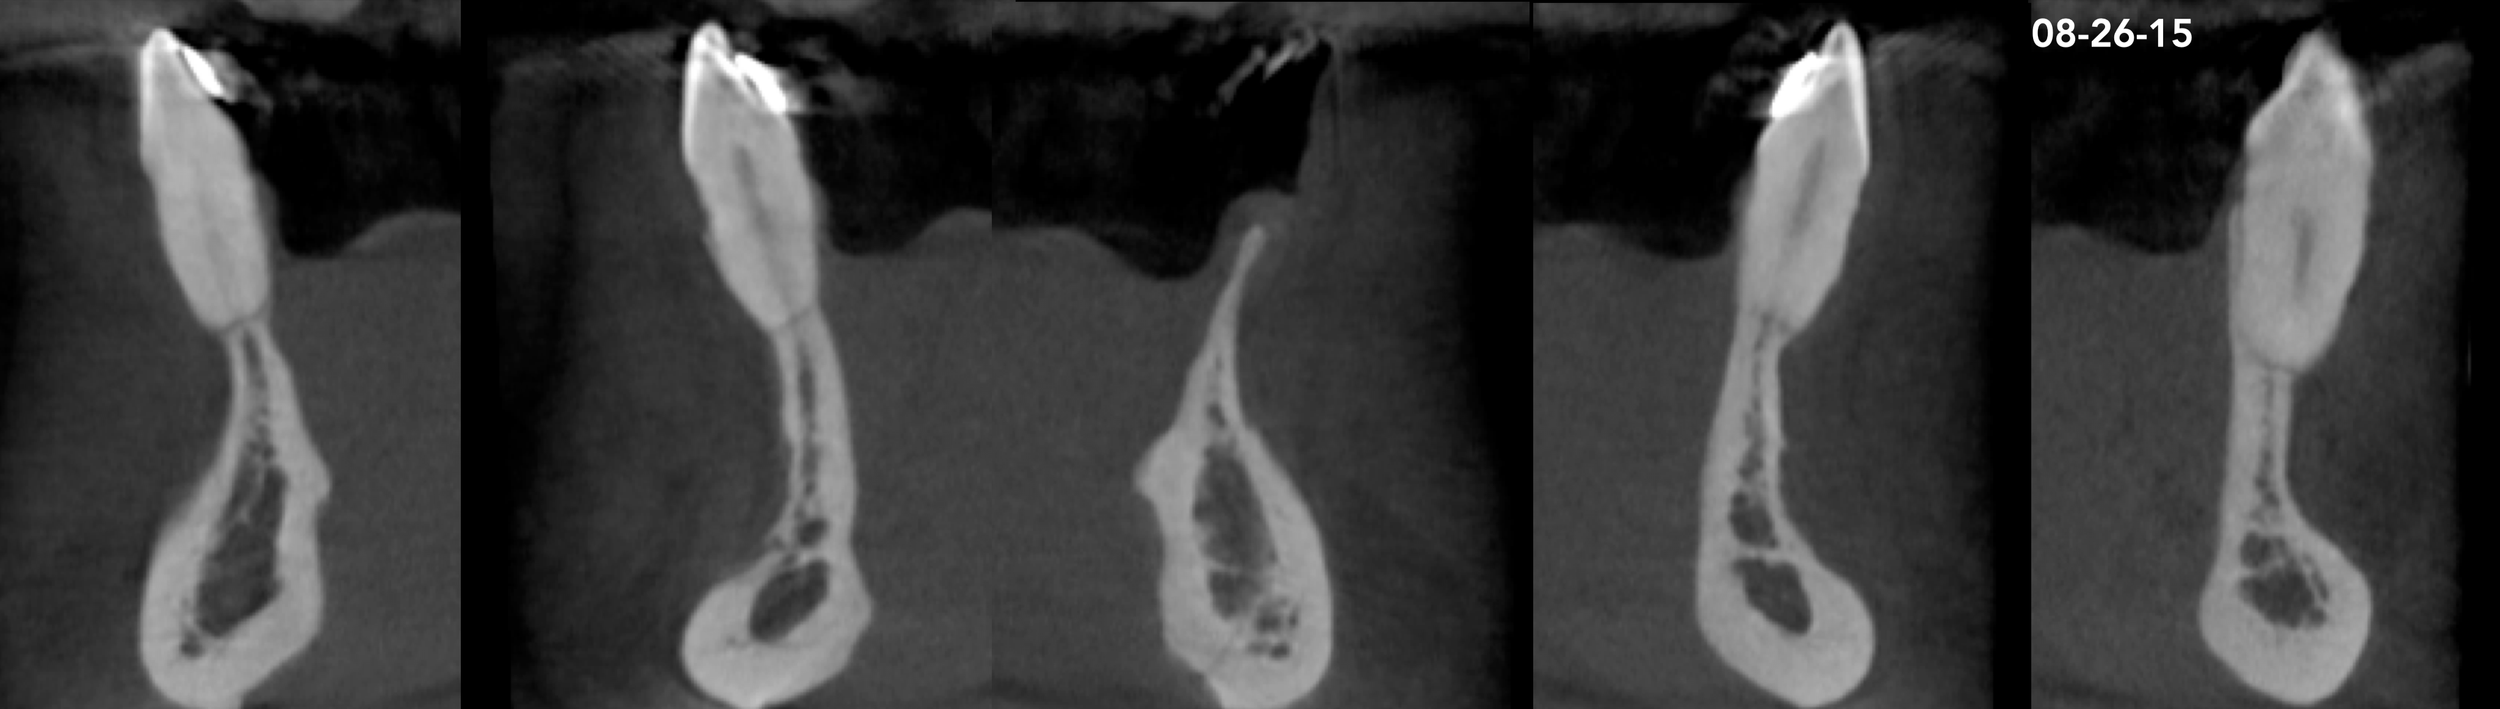

CASE 7. KNIFE-EDGE RIDGE